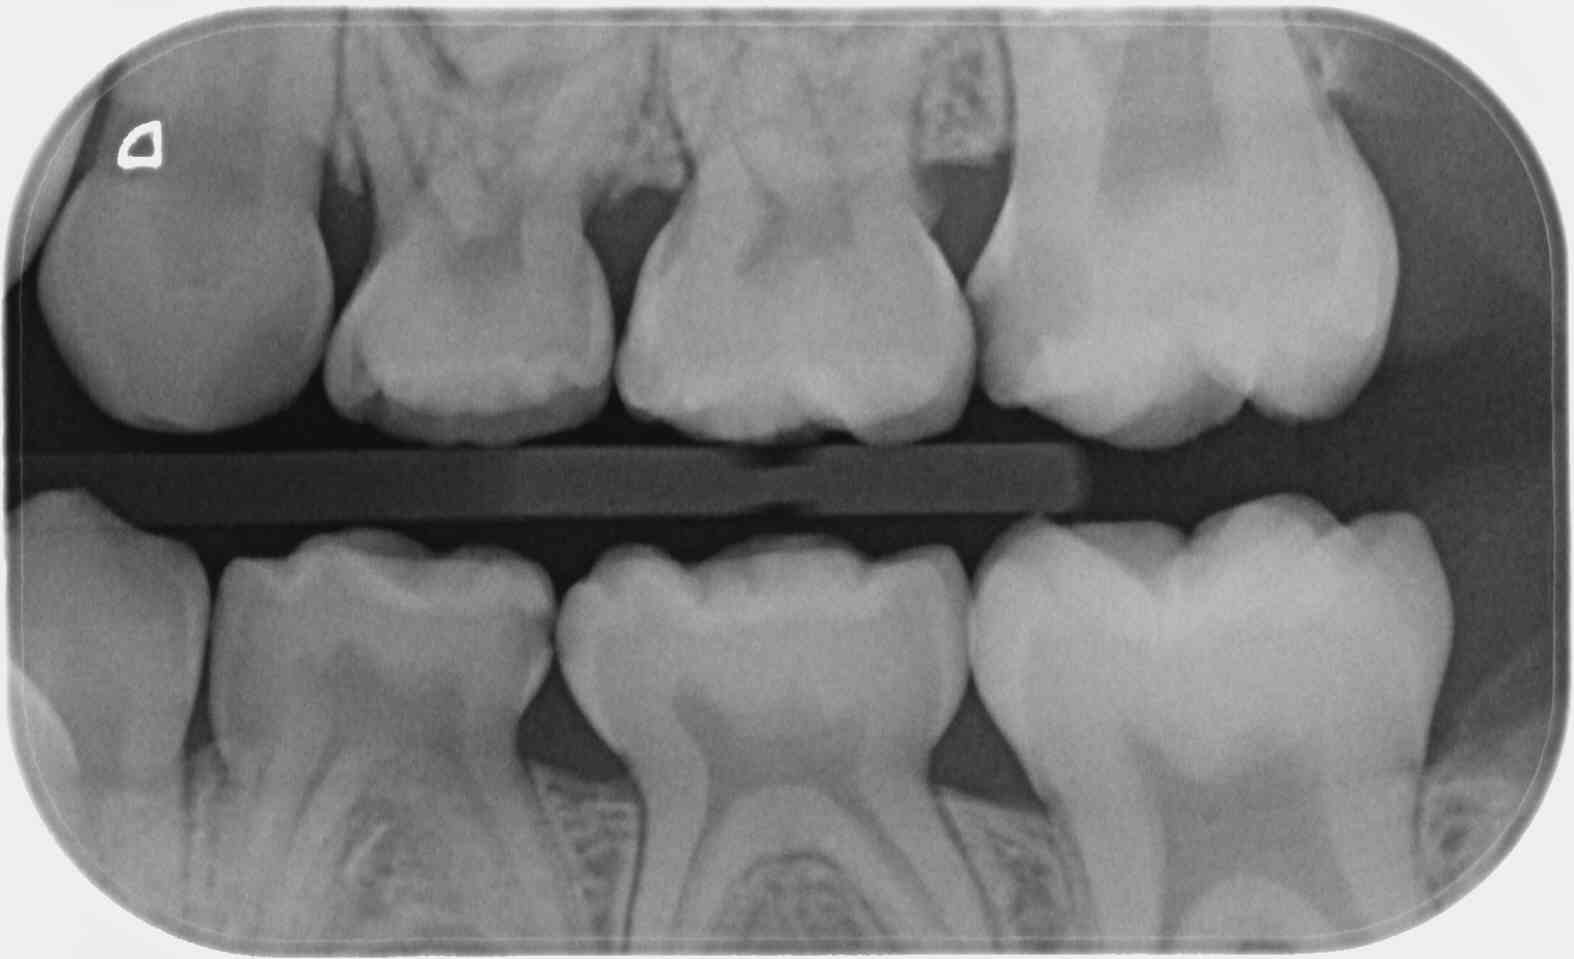

il y a radios retroalveolaire et ou retrocoronaire de deux secteurs : par exemple un bite wing de 16 46 tu cotes deux radio dans le cas où l'indication retrocoronaire est justifiée?

Effectivement, pour les bite-wing, c'est une grossière erreur dans ce qu'il raconte. Un cliché=une cotation. Mon CDC qui a visionné le diaporama, avait relevé la boulette. Et il parait qu'il y en a d'autres...

Oui, 1 cliché bite-wing seul = 1 cotation (équivalent à 1 x Z6), mais 1 cliché bite-wing + 1 rétro sur la 11 = 3 secteurs (équivalent à 3xZ6)

et 1 cliché bite-wing de chaque côté = 4 secteurs (4xZ6).

HBQK443= Radiographies intrabuccales rétroalvéolaires et/ou rétrocoronaires de 4 secteurs distincts de 1 à 3 dents contigües.

Le nombre de cliché n'est pas précisé, 1 bite-wing de chaque côté correspond bien à cette cotation.

Par contre, si dans la même séance je rajoute une rétro sur une molaire déjà comprise dans les bite-wings, alors là je ne la cote pas en plus.